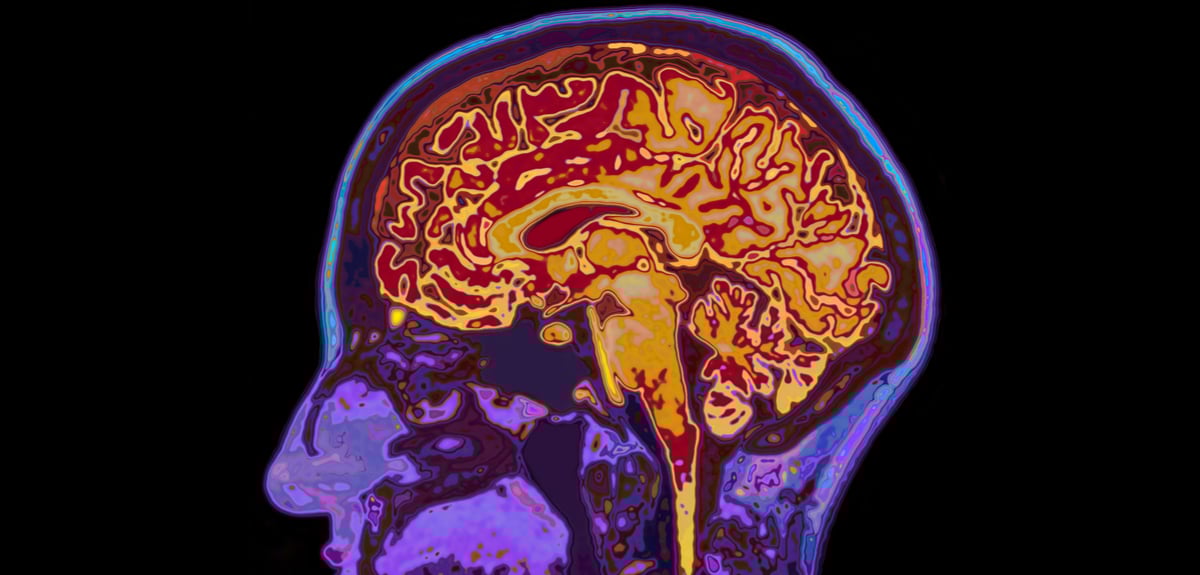

Η διάρκεια μιας ανάμνησης δεν καθορίζεται από μια στιγμιαία απόφαση του εγκεφάλου αλλά από μια σύνθετη και παρατεταμένη διαδικασία που ξεδιπλώνεται σε πολλαπλά επίπεδα. Η νέα μελέτη του Rockefeller University έρχεται να φωτίσει αυτή τη λεπτή ισορροπία, δείχνοντας ότι οι εμπειρίες που τελικά επιβιώνουν στον χρόνο περνούν από μια προσεκτική αξιολόγηση και σταδιακή ενίσχυση, η οποία εξαρτάται από τον τρόπο συνεργασίας διαφορετικών περιοχών του εγκεφάλου.

Τα πειράματα με εικονική πραγματικότητα αποκάλυψαν ότι ο εγκέφαλος δεν αποθηκεύει τις πληροφορίες με ενιαίο τρόπο αλλά ενεργοποιεί διαφορετικά βιολογικά προγράμματα, το καθένα με τον δικό του ρυθμό. Ο θάλαμος φαίνεται πως διαδραματίζει τον κρίσιμο ρόλο της επιλογής, καθώς διακρίνει ποιες εμπειρίες έχουν επαρκές βάρος ώστε να μεταφερθούν στον φλοιό, όπου οι νευρικές συνδέσεις ενισχύονται και η μνήμη αποκτά σταθερό θεμέλιο. Η σταδιακή αυτή πορεία στηρίζεται από τρία μόρια που καθορίζουν τη διάρκεια και την ανθεκτικότητα κάθε ανάμνησης.

Η εικόνα που προκύπτει ανατρέπει την παλαιότερη, απλουστευμένη άποψη για μια μνήμη που εγκαθίσταται μονομιάς και παραμένει αναλλοίωτη. Αντίθετα, η μνήμη παρουσιάζεται ως ένα ζωντανό οικοδόμημα που εξελίσσεται, μεταμορφώνεται και ενισχύεται με τον χρόνο. Η κατανόηση αυτού του μηχανισμού ανοίγει νέες προοπτικές για την έρευνα νευροεκφυλιστικών νόσων, όπου η διατήρηση των αναμνήσεων τίθεται στο επίκεντρο της ανθρώπινης αξιοπρέπειας.